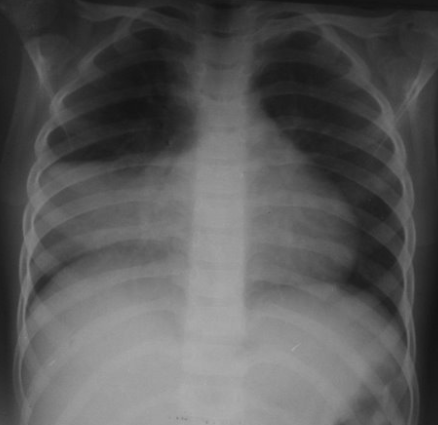

Rx toracică, incidență P-A

DESCRIERE:

pe tot teritoriul pulmonar, bilateral → opacități nodulare multiple de dimensiuni variabile, intensitate medie-mare, omogene, cu contur imprecis delim

confluente

distribuție anarhică

DX: bronhopneumonie

DD:

miliara TBC

MTS pulm hematogene